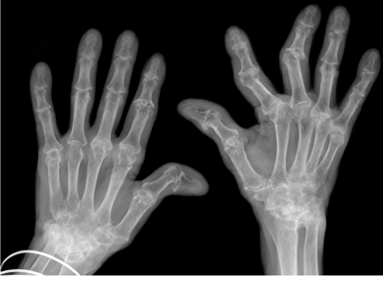

Na maioria dos casos, os sintomas aparecem gradualmente, e podem levar semanas ou meses para que a pessoa a procure cuidados médicos. Nas primeiras fases, geralmente são afetadas as pequenas articulações, especialmente as articulações das mãos e dos pés. Menos frequentemente, pode começar em uma única articulação grande, como o joelho ou o ombro, ou pode passar de uma articulação para outra.

Conforme a condição progride, podem ser acometidas outras articulações dos membros superiores e inferiores. Menos comumente, algumas pessoas têm inflamação nos quadris e na parte superior da coluna vertebral. Os sintomas relacionados às articulações geralmente incluem rigidez, dor, vermelhidão, calor ao toque e inchaço. A rigidez articular é mais incômoda de manhã e após ficar parado por um período de tempo. Embora outros tipos de artrite possam causar rigidez, a rigidez vista na AR muitas vezes persiste por mais de uma hora. Outros sintomas podem incluir fadiga, dor muscular, febre baixa, perda de peso e dormência nas mãos.

Deformidades características da mão podem ocorrer ao longo do tempo em pessoas com AR se a inflamação nas articulações persistir. Os dedos podem parecer dobrados, chamados de deformidades em “boutonniere” ou “pescoço de cisne”, ou estarem desviados em direção ao dedo mínimo.